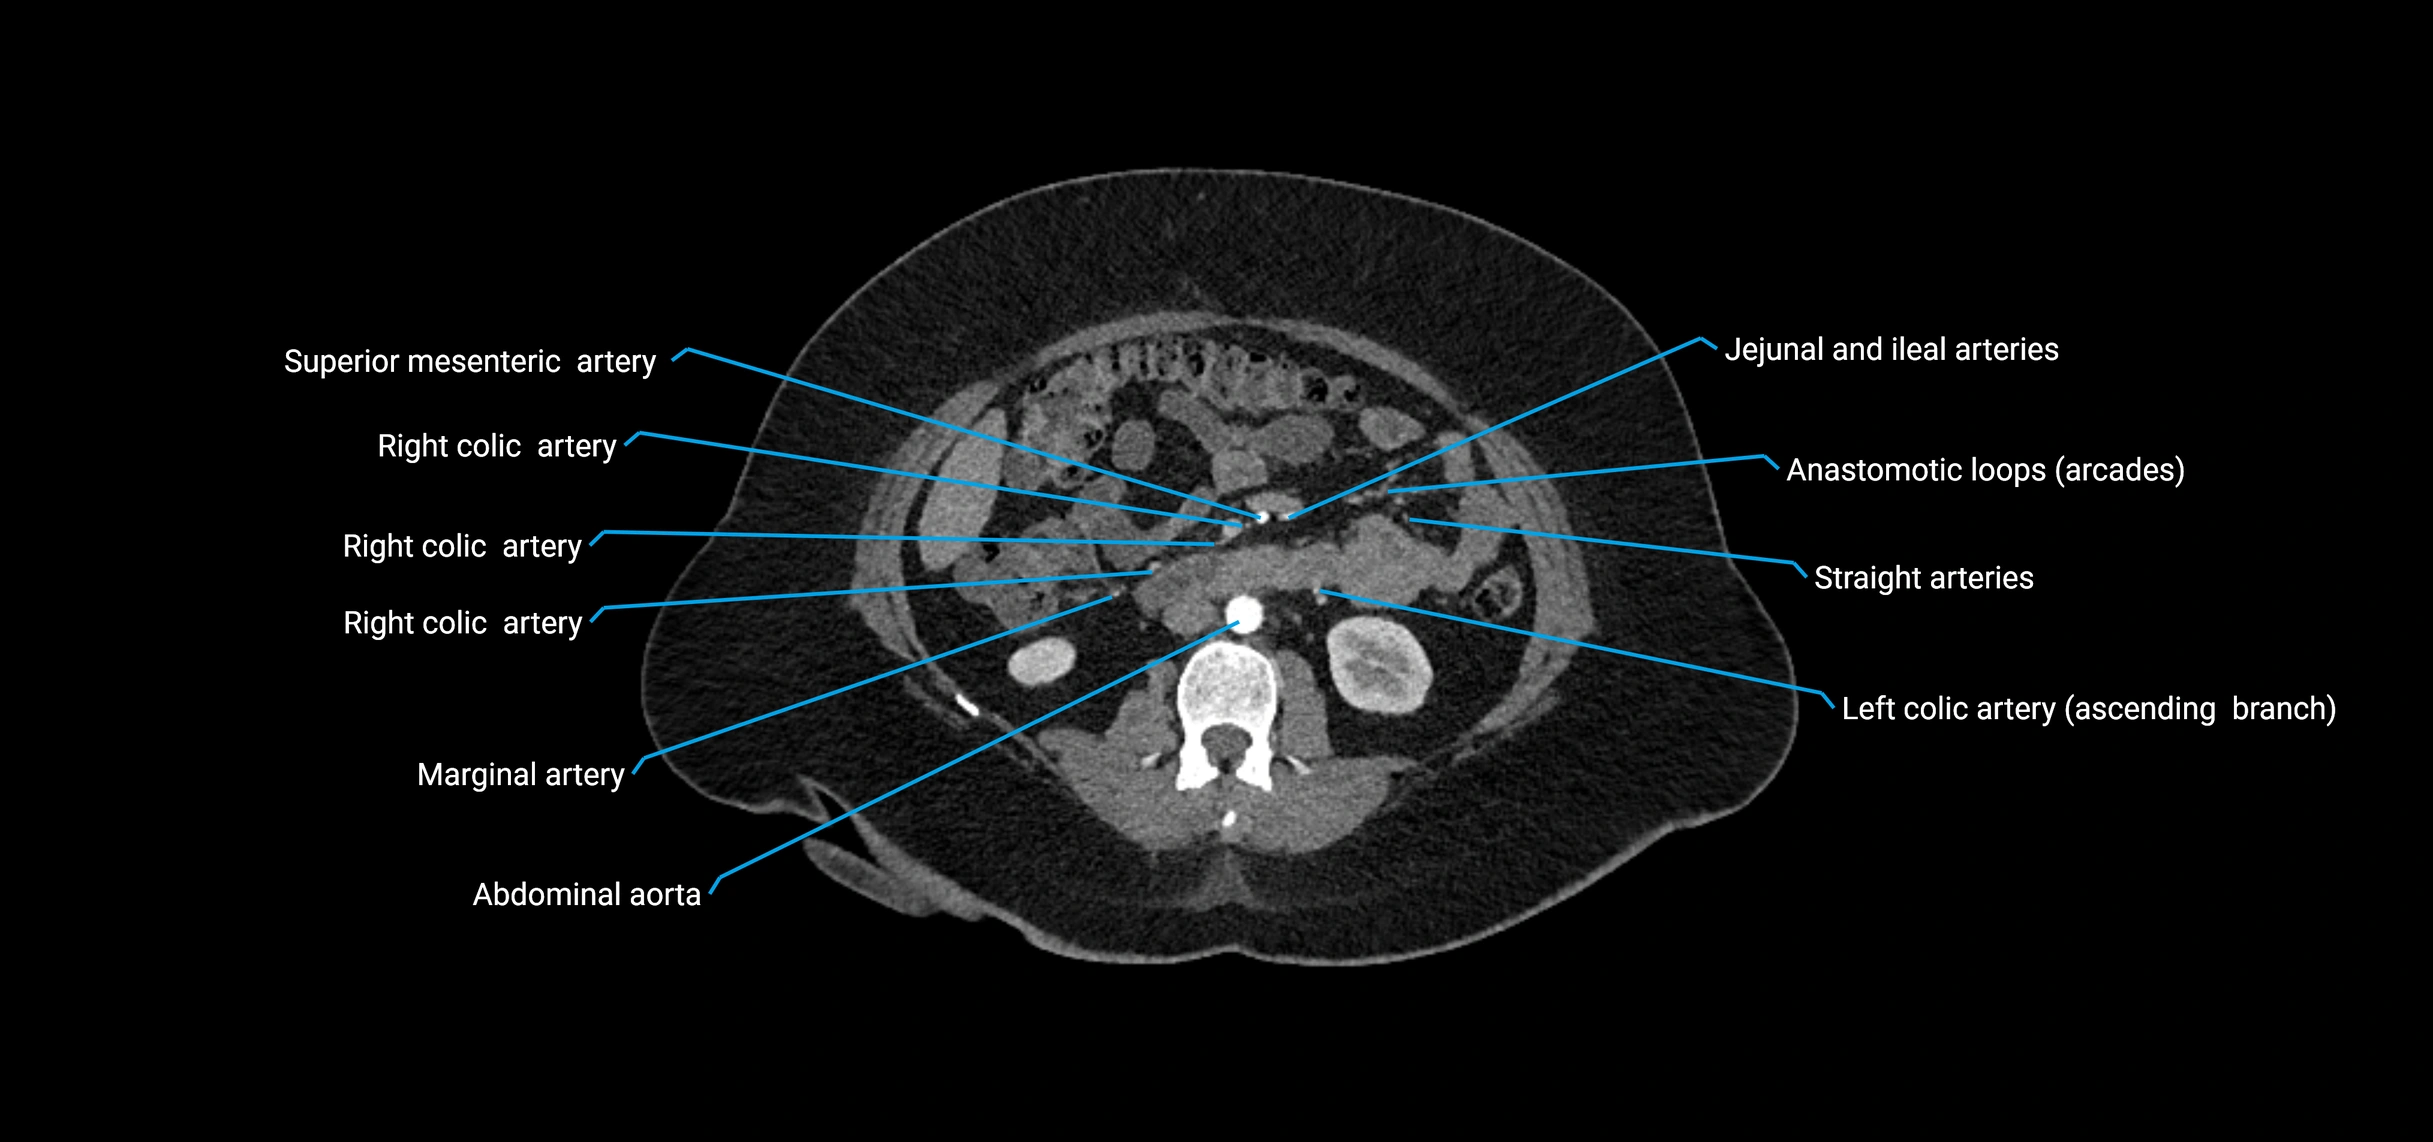

CT images

image

CT Appearance

Non-contrast CT:

• Appears as a tubular soft tissue structure anterior to vertebral bodies

• Calcified atherosclerotic plaques appear as hyperdense foci along the wall

• Useful for screening abdominal aortic aneurysm (AAA) size and mural calcification

Contrast-enhanced CT (CTA):

• Gold standard for abdominal aortic imaging

• Provides excellent detail of lumen, wall, aneurysm, thrombus, and branch vessels

• Multiplanar and 3D reconstructions help in aneurysm measurement, stent graft planning, and dissection evaluation

• Detects acute rupture, traumatic injury, or occlusion with high sensitivity